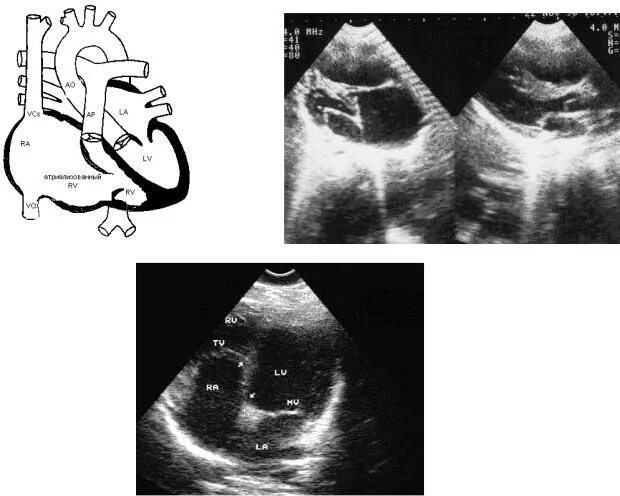

Аневризма мпп без